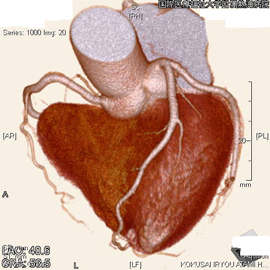

CT検査は体内における各臓器、組織のX線透過量の違いをデータとして収集し、コンピュータで断面像にしています。また、この断面像を細かく収集し積み重ねて画像処理をすることにより、任意の角度から観察することが出来るMPR画像や、3D構築画像を得ることも出来ます。さらに造影剤を使用することによって、血管の3D画像も容易に得ることが出来ます。